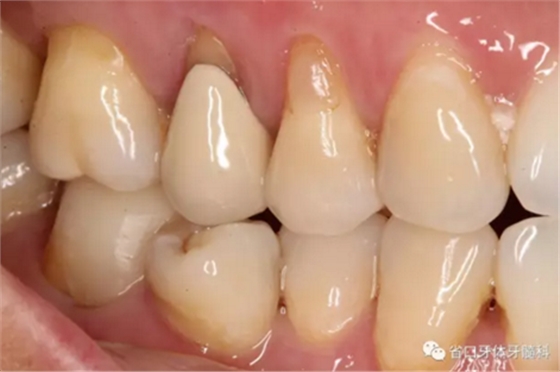

處置:46/清理髓腔,自酸蝕粘接,流動樹脂覆蓋根管口,牙體預備

圖3 牙體預備后,近中頰側牙體缺損平齊齦緣;近頰根管口流動樹脂覆蓋牙膠不足,下次改進

圖4 牙體預備后頰側觀